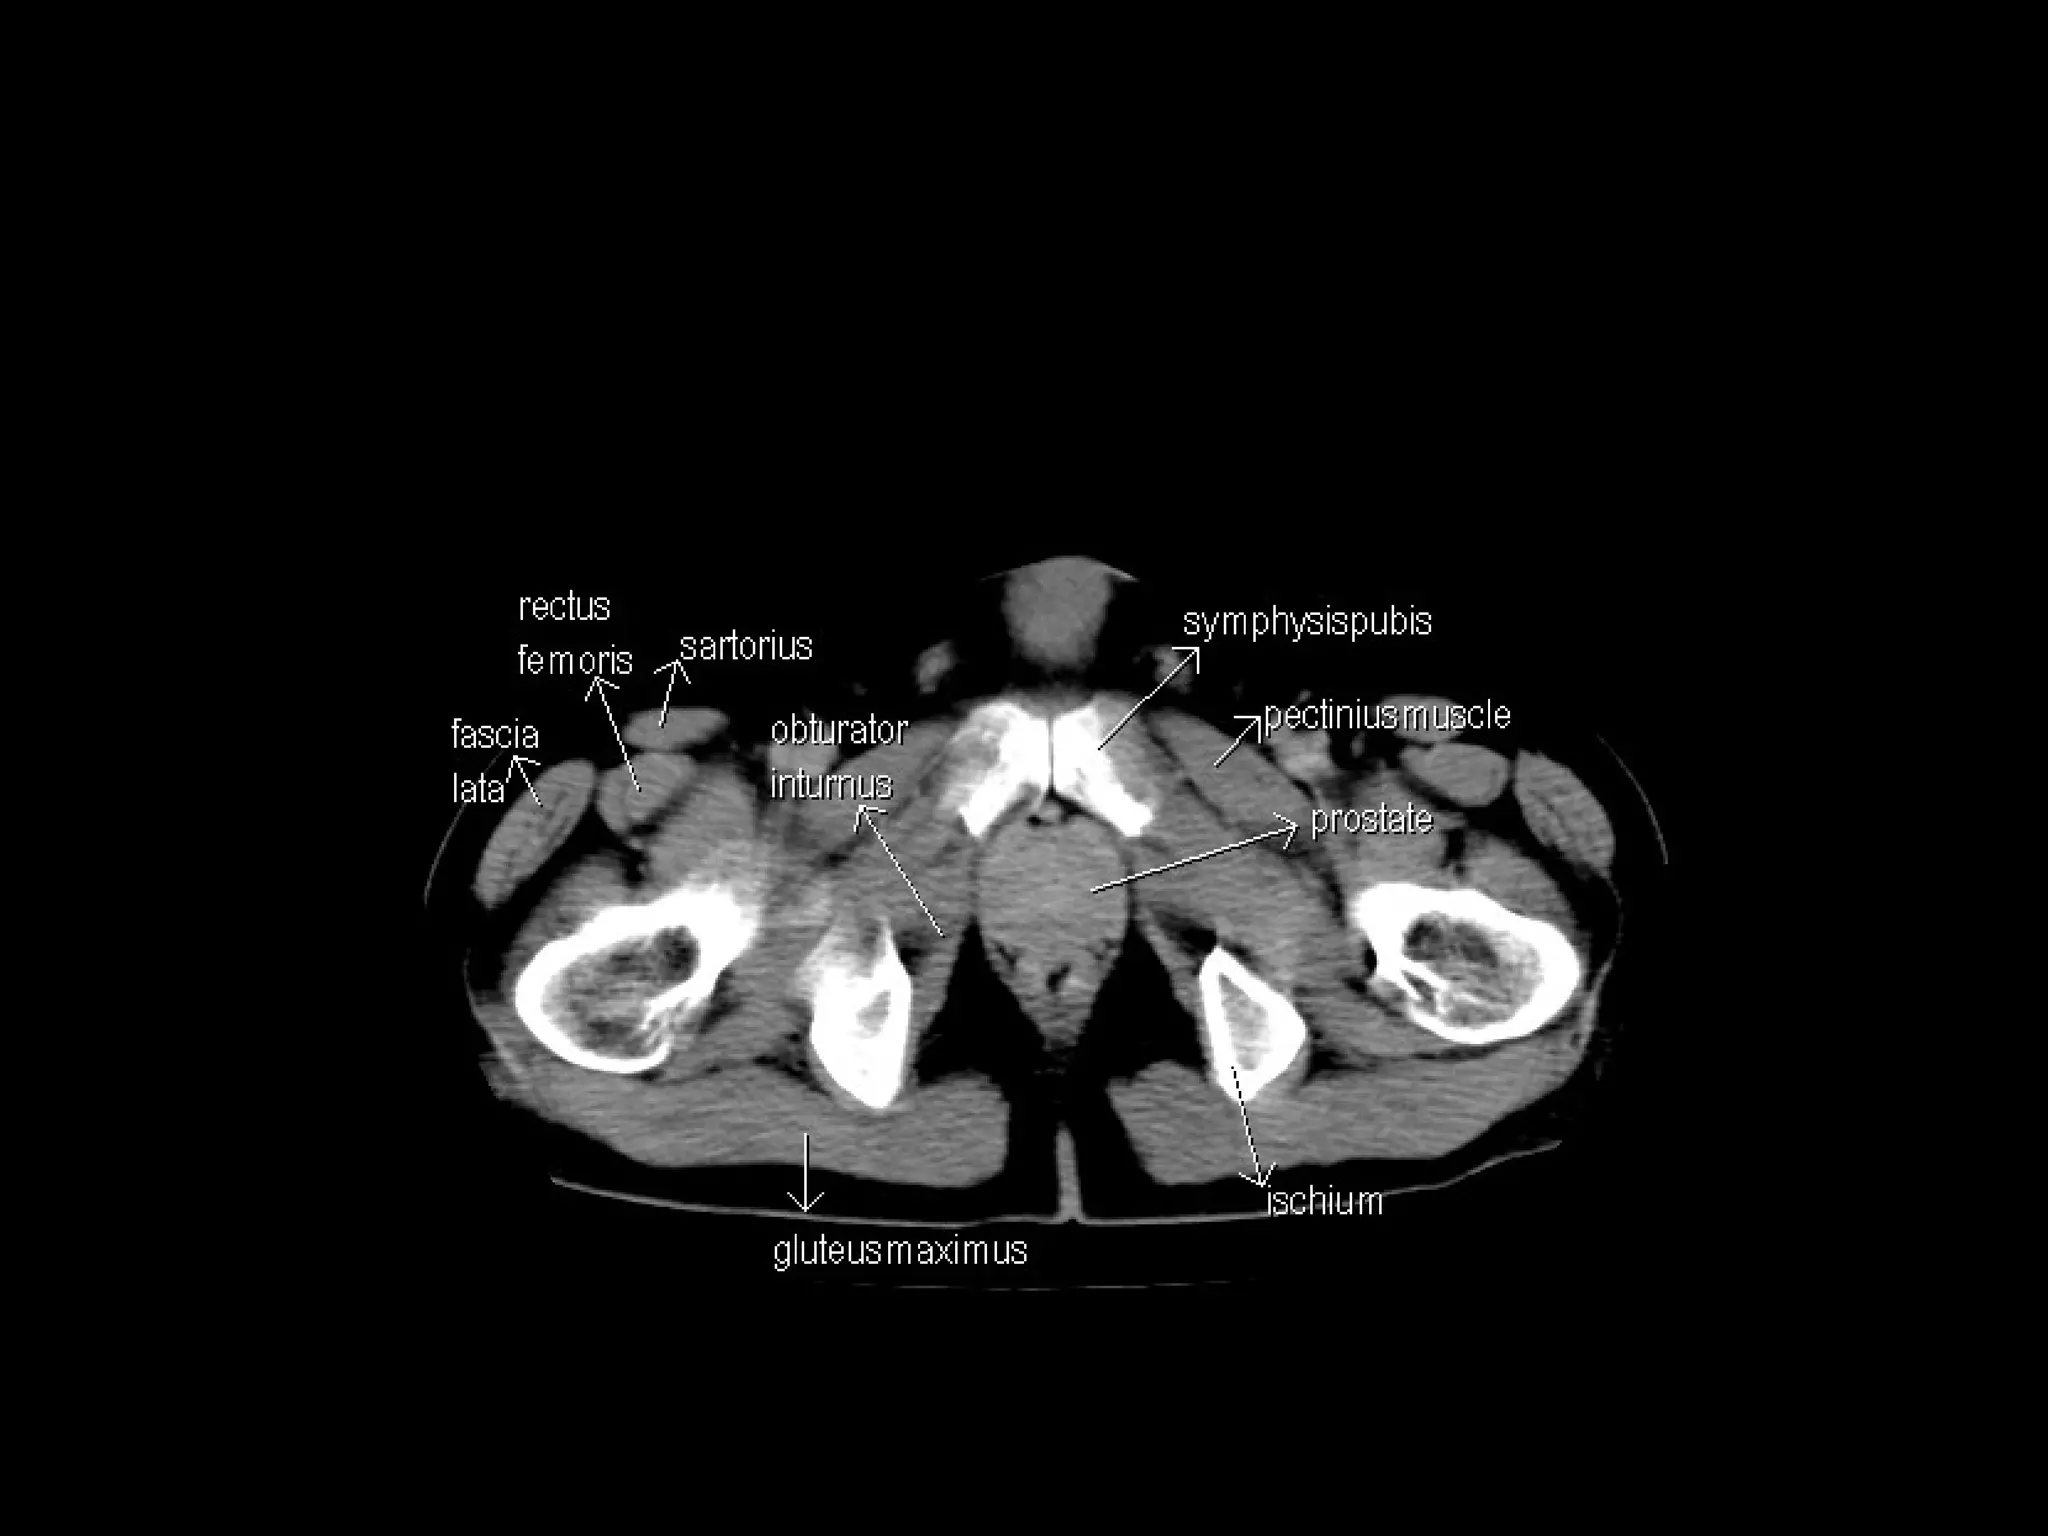

Radiographers are medical professionals who perform diagnostic imaging examinations and procedures to help physicians diagnose and treat diseases. They work under the supervision of radiologists to operate X-ray, CT, MRI, ultrasound and other medical imaging equipment and must have a strong understanding of human anatomy and pathology. Radiographers are responsible for correctly positioning patients, ensuring proper imaging techniques are used, and evaluating the quality of the resulting images.